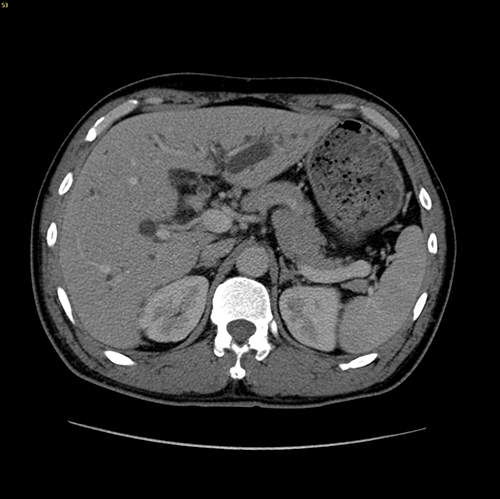

高位胆管癌-胆管癌根治(左半肝+尾状叶切除、右肝管胆肠吻合